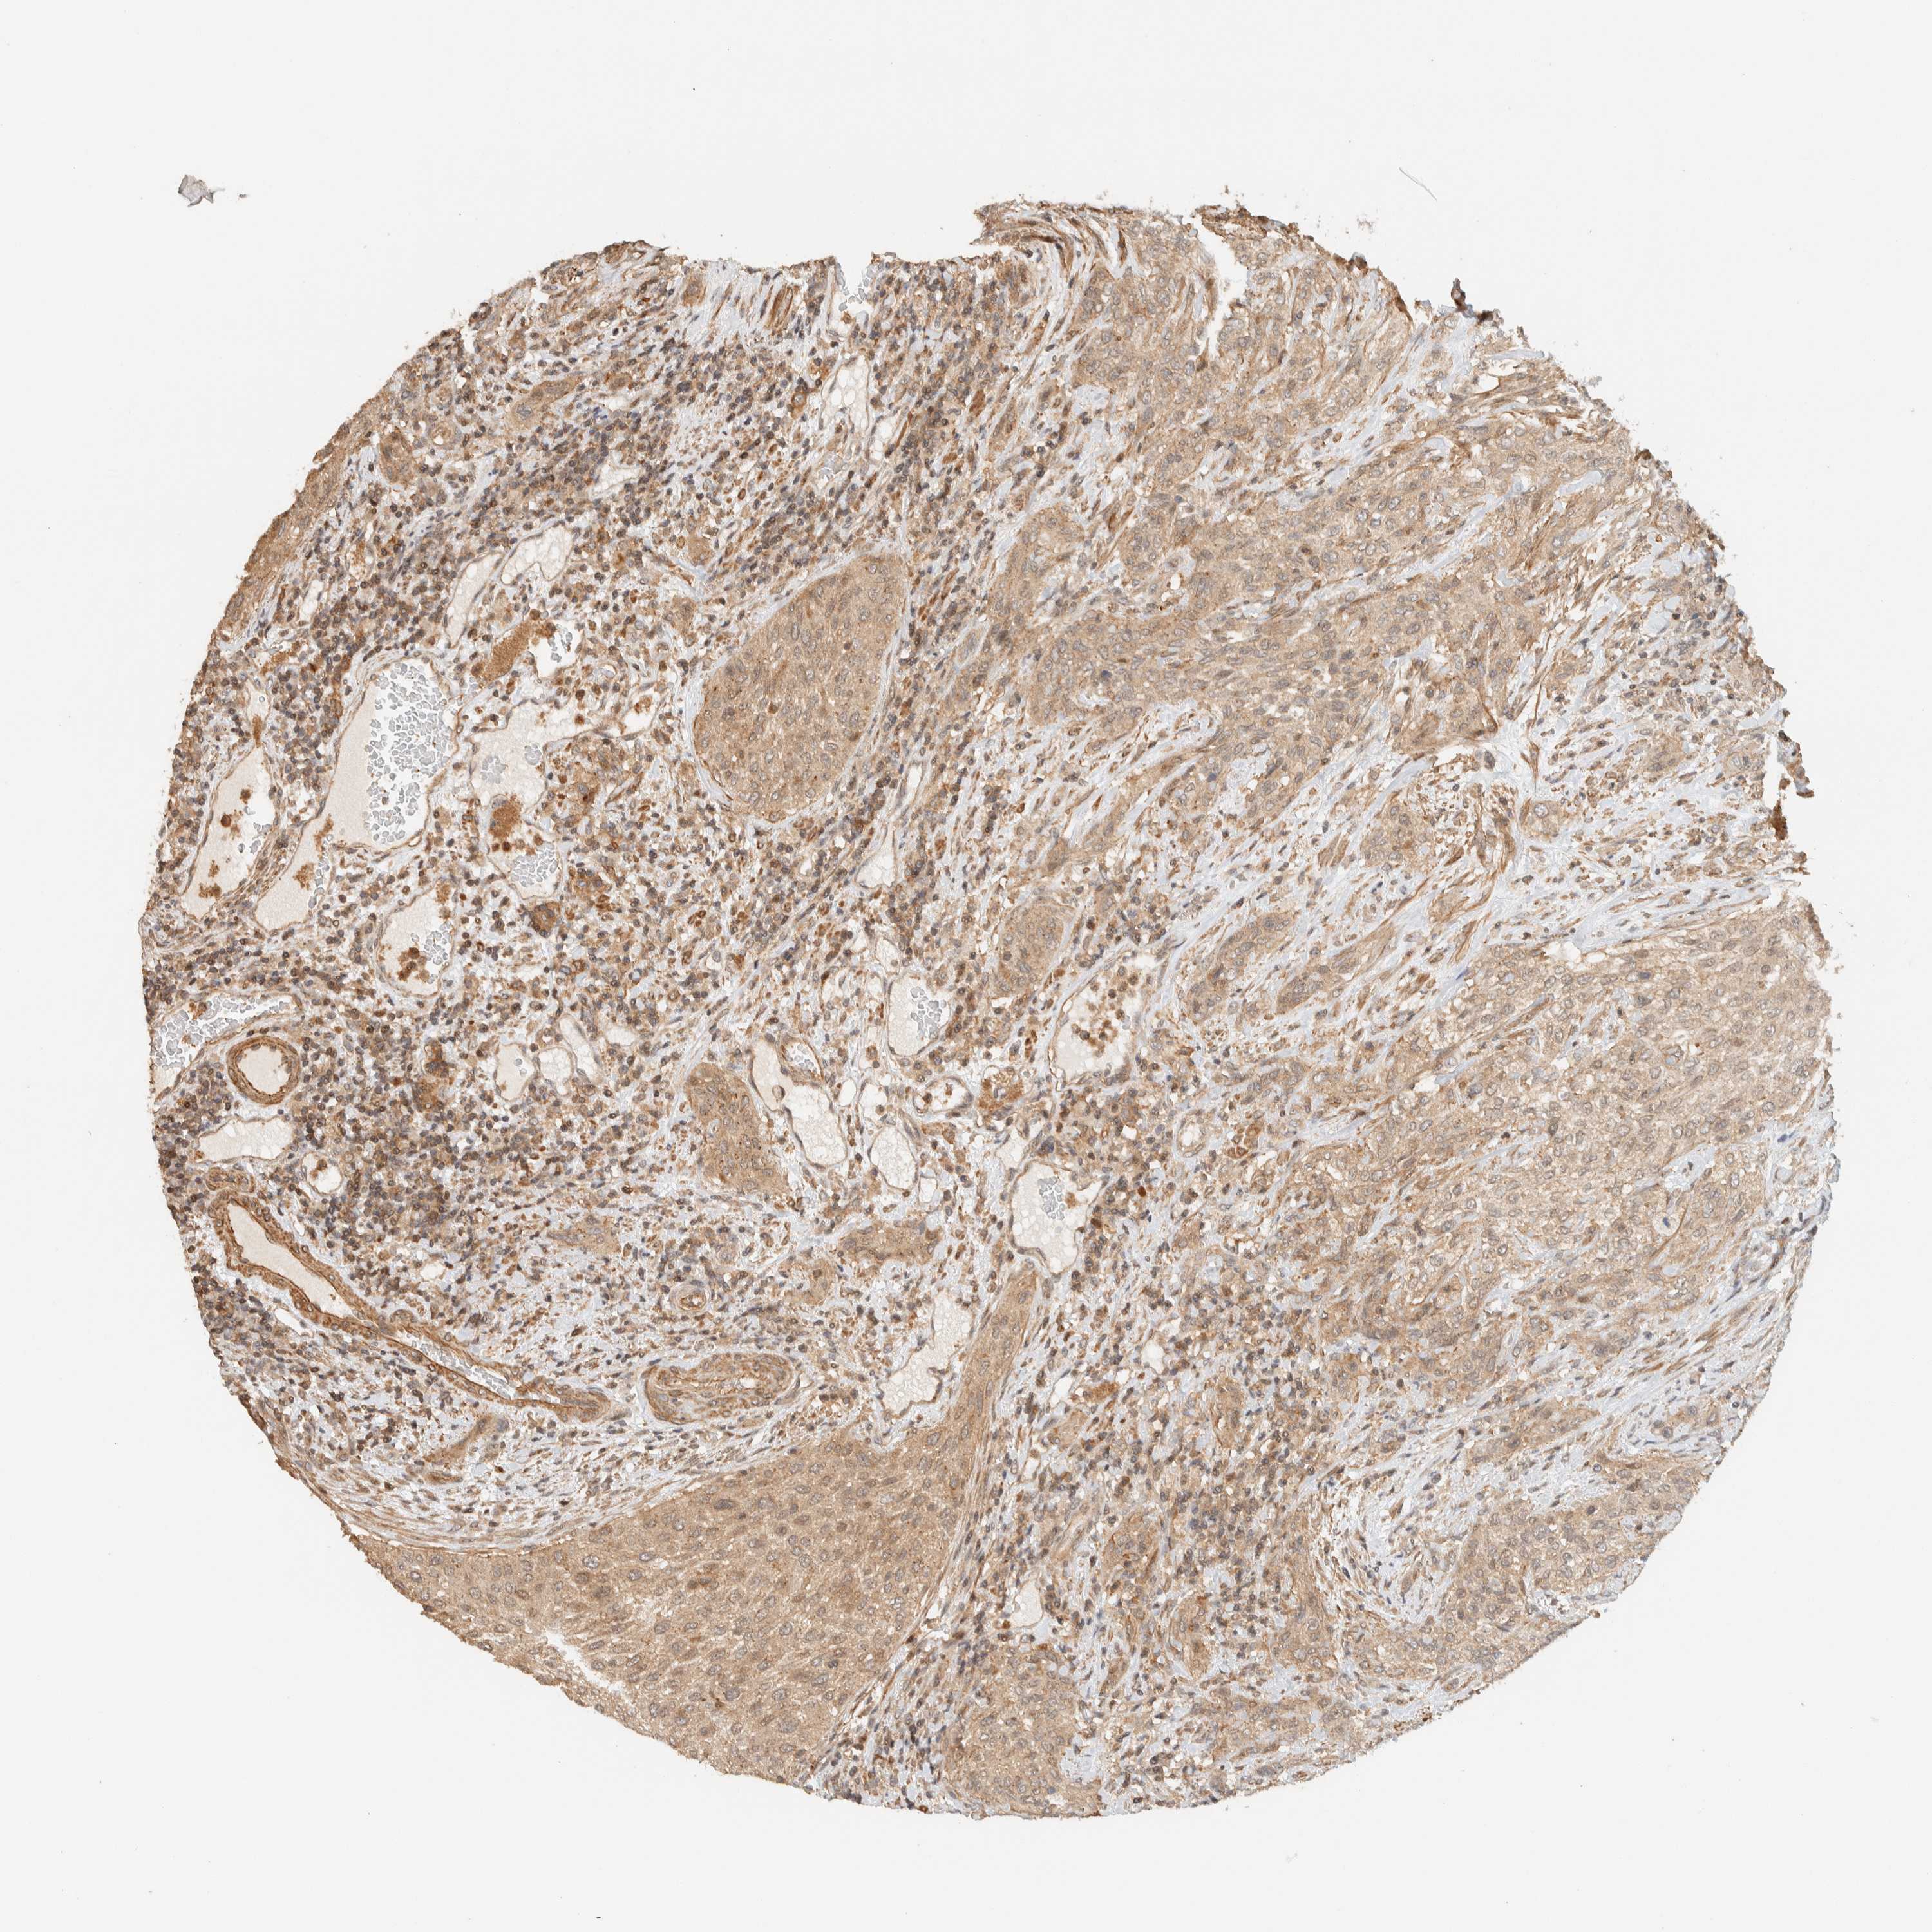

UROTHELIAL CANCER - Protein expressioni

A mouse-over function shows sample information and annotation data. Click on an image to view it in a full screen mode. Samples can be filtered based on level of antibody staining by selecting one or several of the following categories: high, medium, low and not detected. The assay and annotation is described here.

Antibody stainingi

Antibody staining in the annotated cell types in the current human tissue is reported as not detected, low, medium, or high, based on conventional immunohistochemistry profiling in selected tissues. This score is based on the combination of the staining intensity and fraction of stained cells.

Each image is clickable and will lead to virtual microscopy that enables deeper exploration of all samples and also displays staining intensity scores, fraction scores and subcellular localization as well as patient and tissue information for each sample.

Antibody HPA023399

Antibody HPA023822

Staining

High

Medium

Low

Not detected

Intensity

Strong

Moderate

Weak

Negative

Quantity

>75%

75%-25%

<25%

None

Location

Nuclear

Cytoplasmic/membranous

Cytoplasmic/membranous,nuclear

Urothelial carcinoma, Low grade

Urothelial carcinoma, High grade